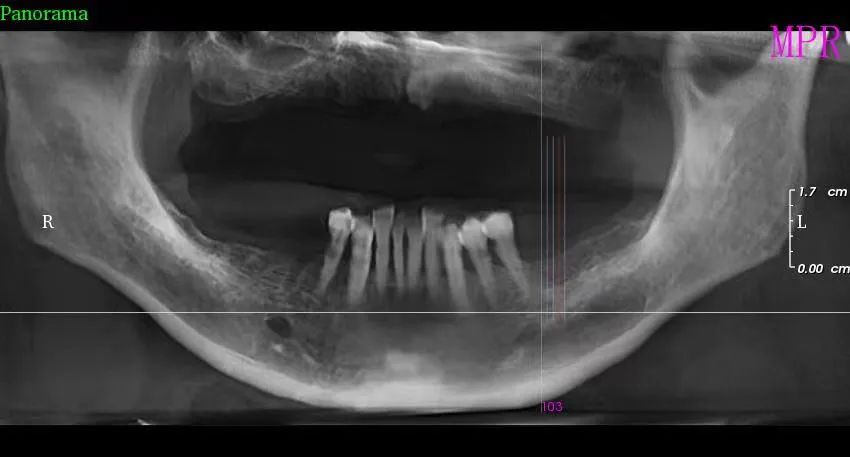

三、種植牙技術

目前,社會上很多人被牙齒缺失所困擾,牙齒缺失不但影響人的咀(jǔ)嚼和語言功能,對於人的麵部美觀也是一種(zhǒng)影響,甚(shèn)至有些人因缺失牙齒而不願意張口說話,種植牙被譽(yù)為人類“第三副牙齒”,因其舒(shū)適、美觀、功能好而被缺牙患者追捧。經衛建委批準,我院(yuàn)於2023年3月18日正式開展種植牙技術,開展當天門診手術7例共計14顆植體,術後1天回訪患者表示無紅(hóng)腫、無疼痛症狀,術後7天回(huí)訪一切良好無異常,術後10天拆線創口愈合良好,自(zì)開展口腔種植手術以(yǐ)來(lái),有(yǒu)許多患者紛紛(fēn)到科裏(lǐ)進行相關谘詢和檢查,更是不斷有患者預約意向種植,我院嚴格按照江西省(shěng)醫療保障局、江西省衛生(shēng)健康(kāng)委員會關(guān)於公布實施口腔種植類醫(yī)療服務價格有關事項的通知—贛醫(yī)保字《2023》3號文件執行操作,在(zài)手術診療中,嚴(yán)格操作流程,減少感染風險。我院口(kǒu)腔種植技術的成功和發(fā)展,不僅完(wán)善了傳(chuán)統(tǒng)牙(yá)齒修複技術的不足,而且在功能與美觀上給了人(rén)們嶄新的體驗,我(wǒ)院(yuàn)致力於提供一站式口(kǒu)腔種植診療(liáo)服務,必將為本縣及周邊缺失牙患者找回(huí)美麗、自信的微(wēi)笑。

案例一

種植前 種植後